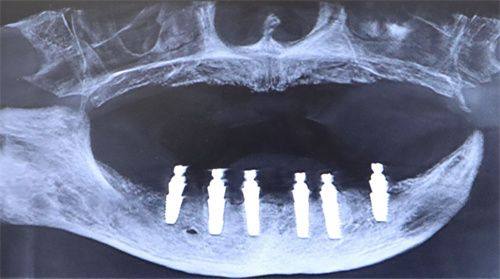

在进行种植牙手术之前,需要进行一系列的术前检查,这是确保手术顺利进行的重要环节。检查项目包括口腔CT、血检测等评估。口腔CT可以帮助医生清晰地了解患者牙槽骨的情况,确定种植体的至佳植入位置;血检测则能检查患者的身体状况,看是否存在影响手术的全身性疾病。这些检查通常需要1 - 2周的时间,因为有些检查结果可能不能马上出来,需要等待一段时间。

术前检查完成且各项指标符合要求后,就可以进行植入手术了。在这个阶段,医生会将种植体置入牙槽骨内。手术时间一般在30 - 90分钟左右,具体时间取决于种植体的数量、植入的难度以及患者的口腔情况。手术过程中,医生会进行局部麻醉,所以患者一般不会感到明显的疼痛。